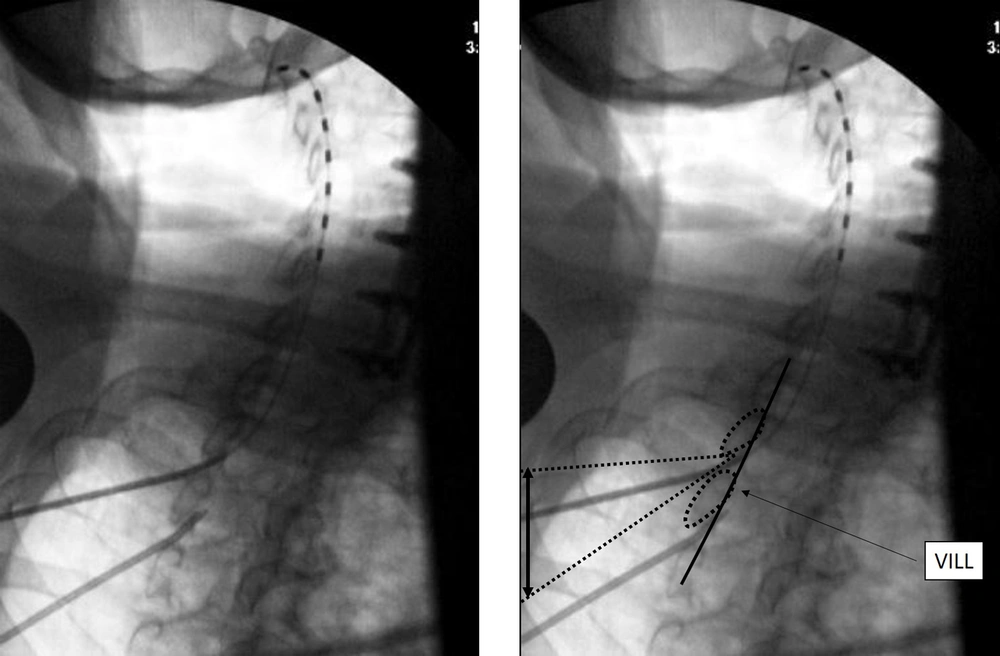

5.2. Cervical Lead Placement with Access from C7-T4 Levels

The needle insertion point is marked about half to one level below the laminar margin. Once a 14G SCS introducer needle is introduced to the top of the inferior lamina, a CLO view at 50 degrees is taken to the contralateral side for depth of needle insertion and trajectory, aiming for the superior edge of the inferior lamina. Loss of resistance is initiated just before the ventral interlaminar line (VILL) and loss expected at, or within 1-3 mm of the VILL. The most important aspect of this technique is to use an optimal obliquity of 50 degrees, or close to it, as the needle tip position depends on obliquity. Other important aspects are to visualize the VILL clearly, not the foramen, and to not advance greater than 2 - 3 mm beyond the VILL without checking other views, clearing the needle, passing the lead and other such maneuvers. The loss can be subtle, and if the needle tip has crossed the VILL lead insertion may be attempted even though the loss has not occurred, as the tip may already be in the epidural space. Lesser degrees of obliquity from the AP make the needle appear deeper to the VILL, thus most needle tips will be in Zone 3 at an obliquity of 40 degrees (14). Lateral view is helpful in confirming dorsal epidural space lead localization. The SCS lead placement in CLO view is shown in Figure 1.